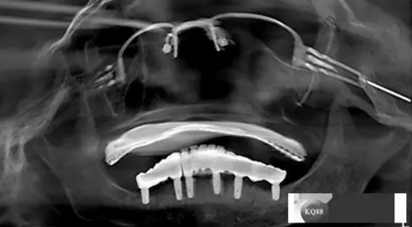

戴牙:試戴,拍片確定邊緣密合后調(diào)整咬合,試戴一周后患者適應(yīng),咬合良好,基臺(tái)加力30N.CM,粘接劑粘固,去除多余粘結(jié)劑,拍片確定有無(wú)粘接劑殘留,并進(jìn)一步微調(diào)咬合

6)6個(gè)月后復(fù)查,修復(fù)體密合性均良好,修復(fù)效果符合預(yù)期,醫(yī)囑患者做好口腔衛(wèi)生預(yù)防種植體周?chē)?/p>